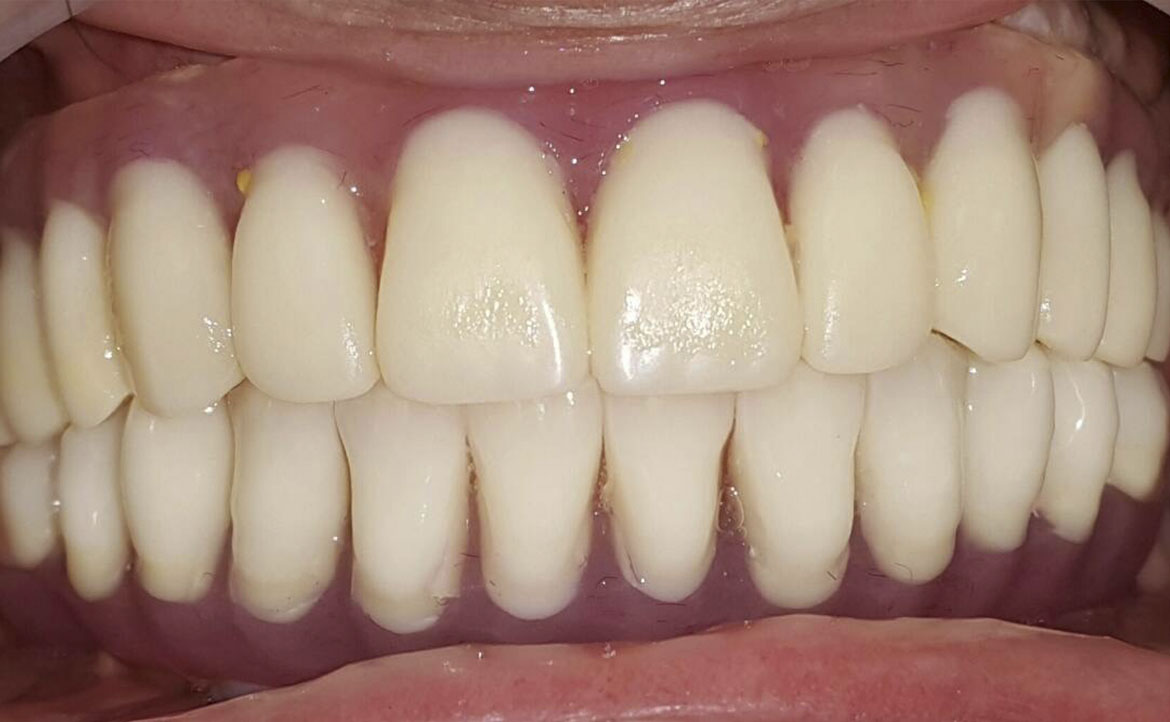

Un tale pezzo protesico ripristina l'integrità delle arcate dentarie. Una protesi mobile correttamente realizzata migliorerà esteticamente i lineamenti del viso del paziente, consentirà il ripristino della funzione masticatoria e migliorerà la fonazione.